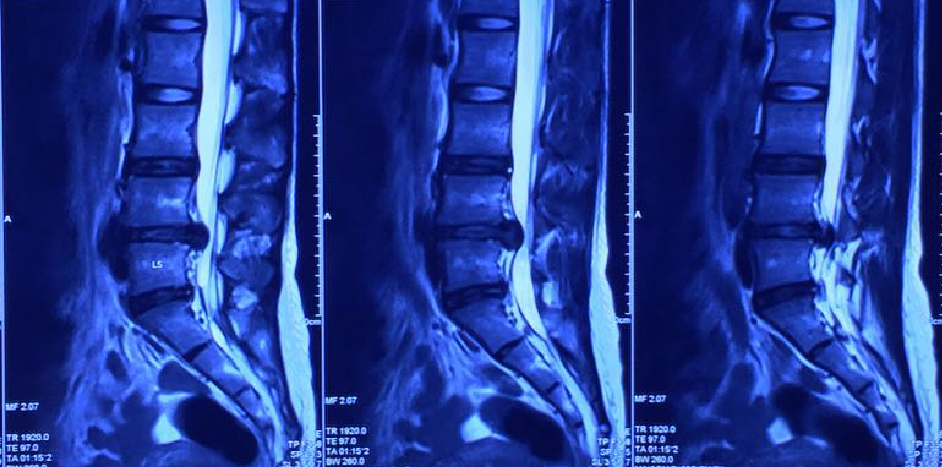

圖說 MR 1、 MR2

2011年8月嚴重腰部第四、第五節椎間盤突出。